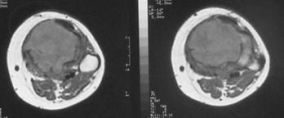

MRI (Magnetic resonance imaging / Manyetik rezonans görüntüleme)

Tümörün yumuşak doku ve kemik iliğinde yayılımını değerlendirmek için MRI kullanılır. Düz grafiden sonra yapılması gereken incelemedir. Ancak MRI bazen gereğinden fazla ayrıntı gösterebilir. Örneğin osteoid osteoma gibi bazı tümörler aşırı ödem nedeni ile kötü huylu tümörlere benzer görüntü verebildiğinden yanıltıcı olabilir.